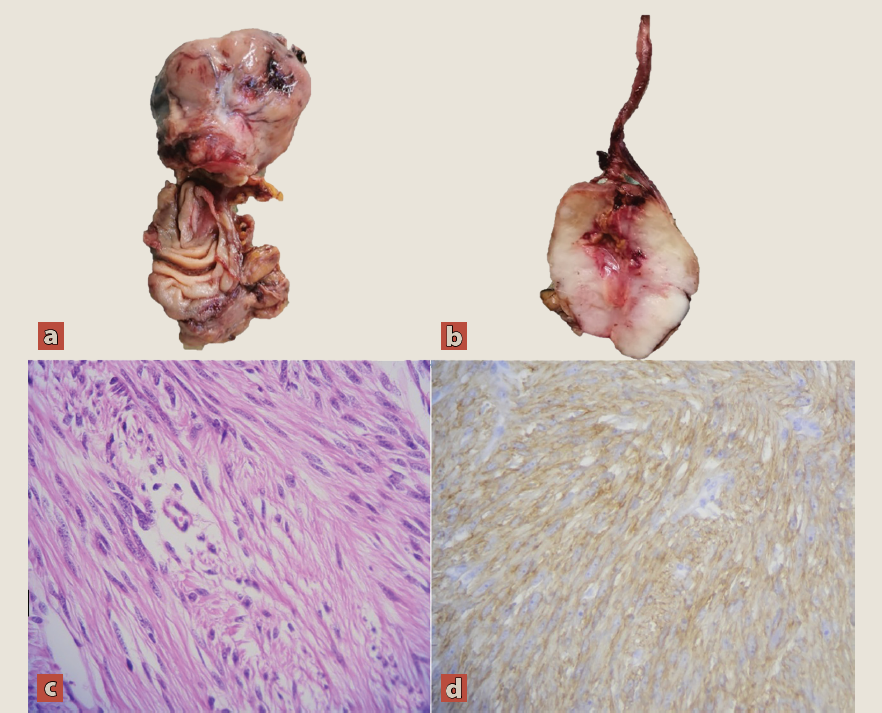

La pieza quirúrgica fue enviada a patología para su análisis, donde reportaron un segmento de intestino delgado de 4.3 × 2.1 cm con tipo histológico de tumor del estroma gastrointestinal de células fusiformes de 3.9 × 3.8 cm (figura 3). Inmunofenotipo de las células neoplásicas (por inmunohistoquímica): CD117: positivo; DOG1: positivo; CD34: negativo; actina de músculo liso: negativo; S100: negativo; mitosis: 1 por campo de alto poder; bordes quirúrgicos a 1.8 cm y a 2.7 cm, negativos a neoplasia.

Figura 3 a y b) Imagen macroscópica: Tumor del estroma gastrointestinal de células fusiformes de 3.9 × 3.8 cm, se observa conducto onfalomesentérico adherido al borde del tumor. Imagen microscópica: c) El examen histopatológico revela un tumor del estroma gastrointestinal de células fusiformes, con inflamación aguda y crónica; pueden observarse células gigantes multinucleadas de tipo cuerpo extraño y peritonitis fibrinopurulenta. d) La inmunohistoquímica muestra CD117 positivo (c-kit)

Dentro de las características patológicas adicionales, el tumor presentó inflamación aguda abscedada y crónica con inflamación granulomatosa con células gigantes multinucleadas de tipo cuerpo extraño y peritonitis fibrinopurulenta. El intestino presentó además edema y congestión submucosa, congestión vascular transmural y hemorragia reciente focal. Se observaron también datos de peritonitis fibrinopurulenta que se extendía al borde quirúrgico a 1.8 cm.